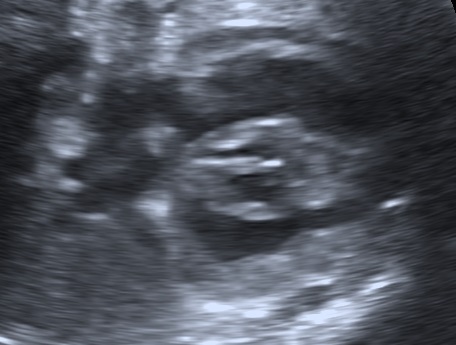

Below a case of fetal hypertrophic cardiomyopathy by maternal gestational diabetes mellitus in the 35w4d.

Thickening of the interventricular septum, and to a lesser extent the ventricular free walls (Hornberger, 2006). This thickening can lead to ventricular outflow obstruction (Stuart et al, 2010). The thickness of the interventricular septum should be measured at the four chamber view, just below the level of the atrioventricular valves in end diastole (Kulkarni et al, 2017).